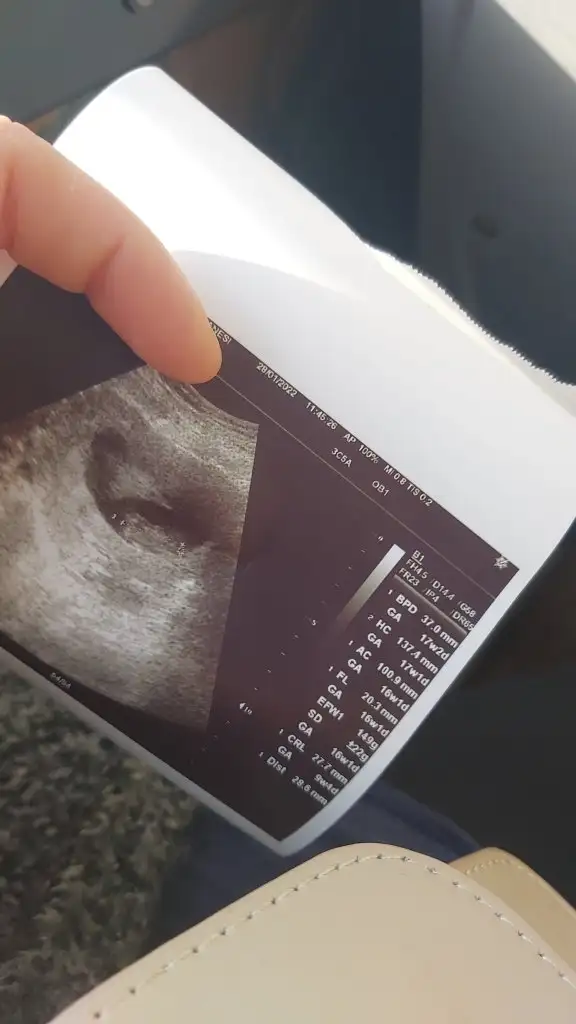

S sessiz51 Yeni Üye Kayıtlı Üye 25 Aralık 2021 3 0 1 35 7 Ocak 2022 Konu Sahibi Konu Sahibi sessiz51 #4 Merhabalar 12+3 günlük olduk. Cinsiyetini öğrenemedik hala. Sizlerin tahminini öğrenebilir miyim.

M Mavistez Popüler Üye Kayıtlı Üye 14 Ekim 2018 6.822 6.103 198 8 Ocak 2022 Konu Sahibi Konu Sahibi sessiz51 #5 sessiz51 .!.: Merhabalar 12+3 günlük olduk. Cinsiyetini öğrenemedik hala. Sizlerin tahminini öğrenebilir miyim.Eki Görüntüle 2983804 Genişletmek için tıkla... Erkek gibi ama emin olamadım canm öğrenince dönüş yap unutmazsan gönlüne göre sağlıklı olsun inşallah

sessiz51 .!.: Merhabalar 12+3 günlük olduk. Cinsiyetini öğrenemedik hala. Sizlerin tahminini öğrenebilir miyim.Eki Görüntüle 2983804 Genişletmek için tıkla... Erkek gibi ama emin olamadım canm öğrenince dönüş yap unutmazsan gönlüne göre sağlıklı olsun inşallah